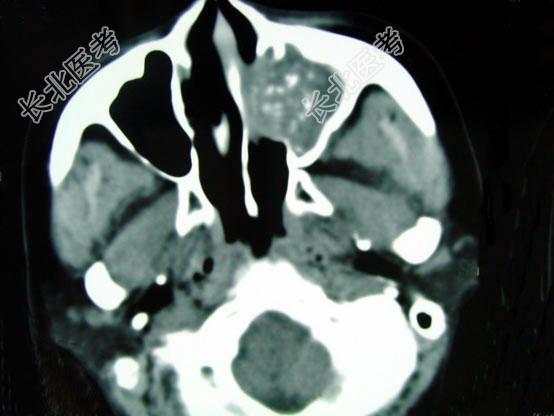

- 单项选择题男,41岁, 左侧鼻腔胀痛半年余,CT检查如图, 最可能的诊断是 ( )

A、出血坏死性息肉

B、化脓性鼻窦炎

C、过敏性鼻窦炎

D、真菌性鼻窦炎

E、上颌窦癌